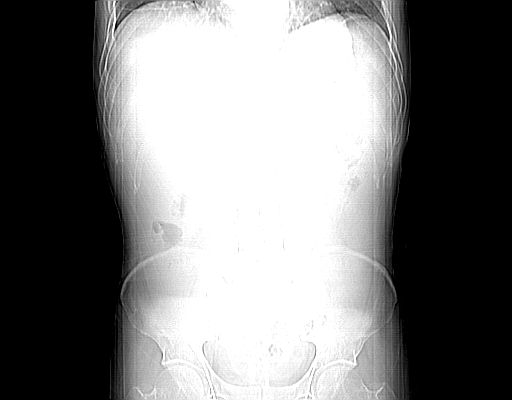

男,55岁,发现“肝硬化”5年,现腰疼、腹胀10余日,巩膜黄染、腹稍胀,肝肋下3指,质硬无压疼,移动性+,血生化:总胆、直胆、间胆均升高。

肝硬化,脾大,腹水

肝脾肿大,脂肪肝,腹水。建议增强除外肝癌。

腹部病变,ct平扫如同隔靴搔痒,建议增强后上传资料。